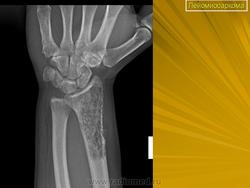

Внутрикостная лейомиома

https://www.ncbi.nlm.nih.gov/pmc/articles/PMC5040582/

Дооперационные рентгенограммы.